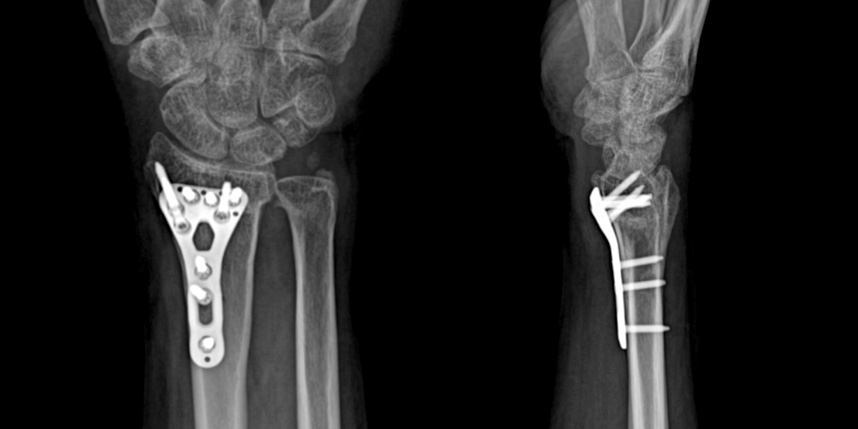

손목 골절